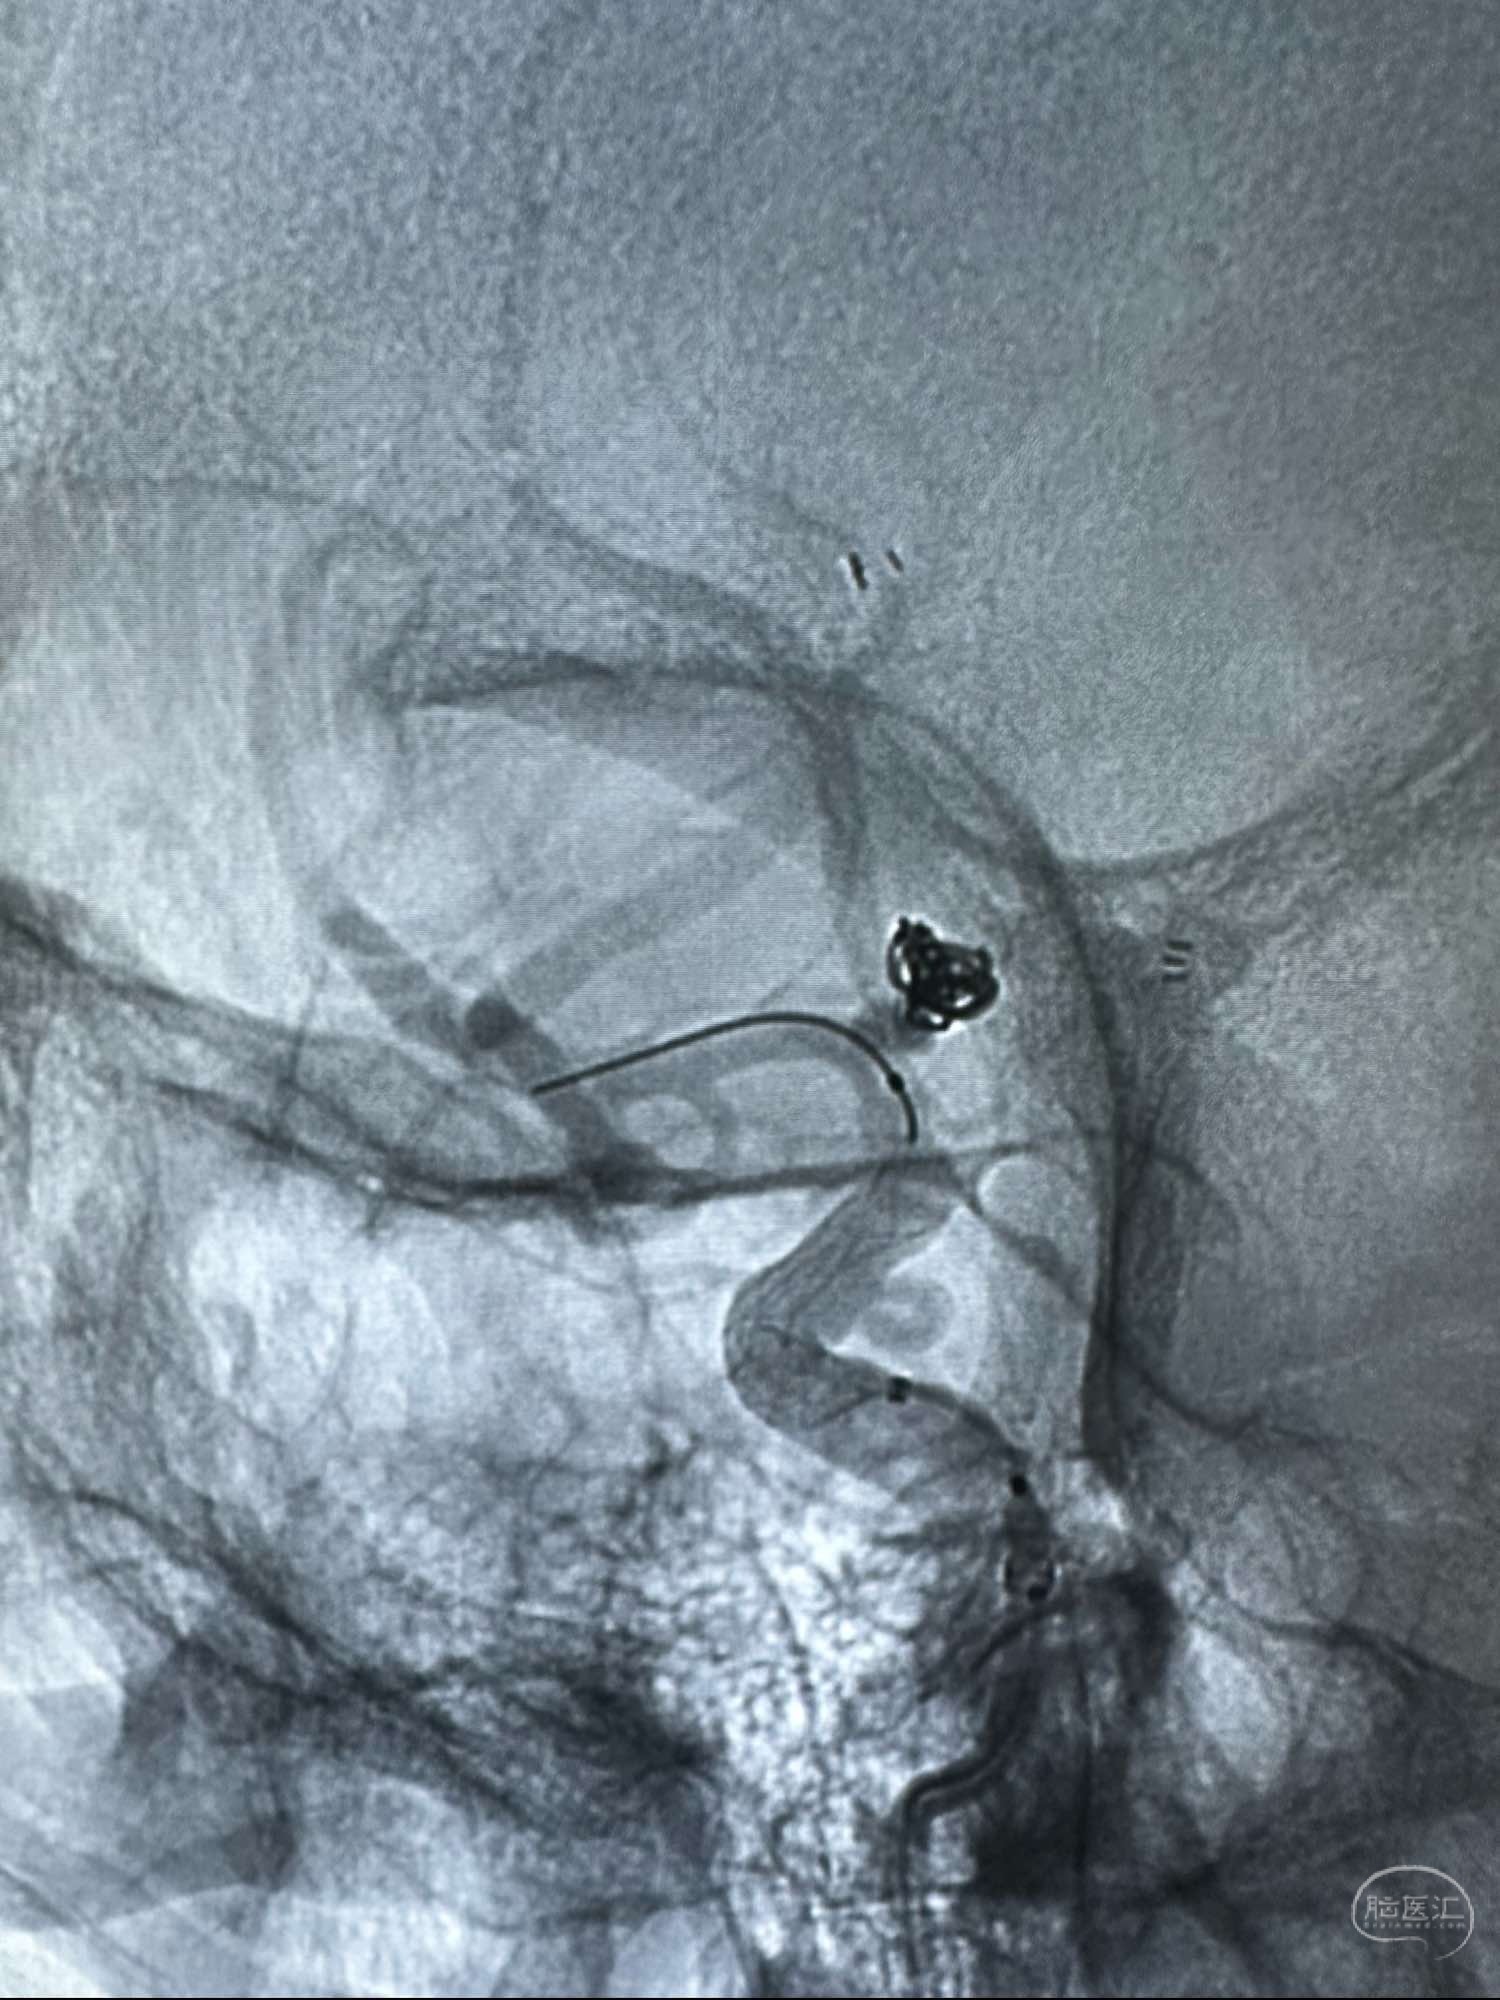

动脉瘤已经完全滞留明显

造影计滞留明显

正位

侧位

外院会诊,右侧眼动脉段动脉瘤,给予Evolve 密网支架处理,术后人无特殊

动脉瘤已经完全滞留明显

造影计滞留明显

正位

侧位